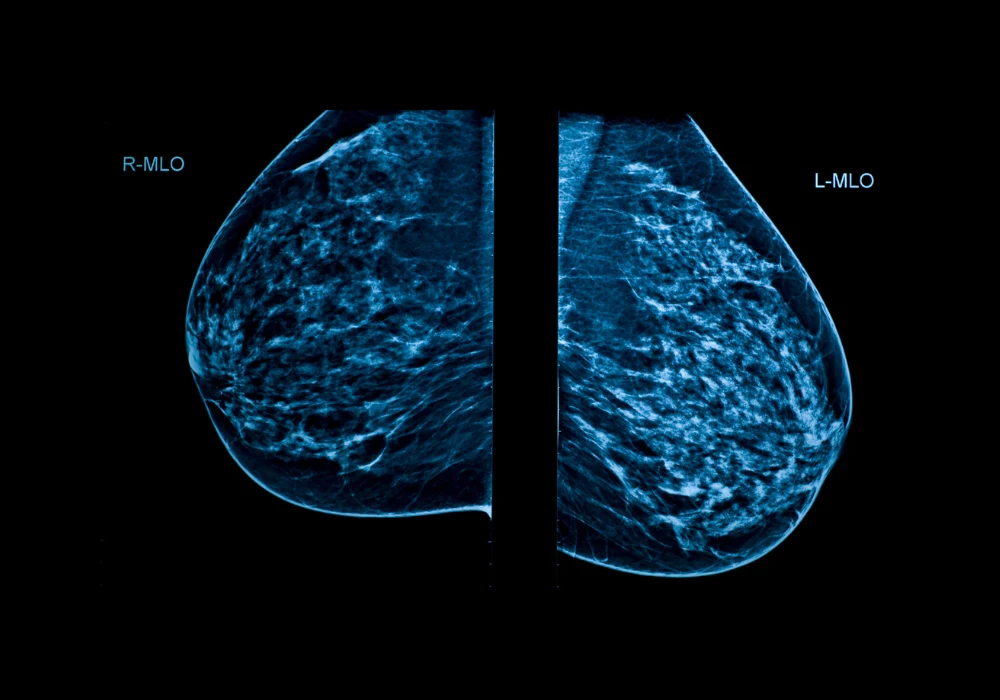

Breast cancer is the most frequently diagnosed cancer among women worldwide. Mammographic screening remains a key strategy in early detection, helping reduce mortality and morbidity. However, limitations such as false-positive and false-negative results, overdiagnosis and radiologist workload continue to challenge screening programmes. Furthermore, a shortage of trained breast radiologists exacerbates these issues. Artificial intelligence, particularly models based on deep learning, has emerged as a promising approach to assist radiologists by improving diagnostic accuracy and efficiency. Using retrospective screening data from BreastScreen Norway, two AI models—one commercially available and one developed in-house—were evaluated to assess their ability to detect breast cancer and accurately localise suspicious findings on mammograms.

The study included 129,434 screening mammograms from 42,300 women aged 50–69 years, collected between 2008 and 2018. Model A, a commercially available tool (Lunit INSIGHT MMG), and Model B, developed in-house by the Norwegian Computing Center, were evaluated as stand-alone readers. Their performances were benchmarked against two detection thresholds, set at 3.2% and 11.1% of the highest AI scores, corresponding to the recall and consensus rates, respectively, in the study population.